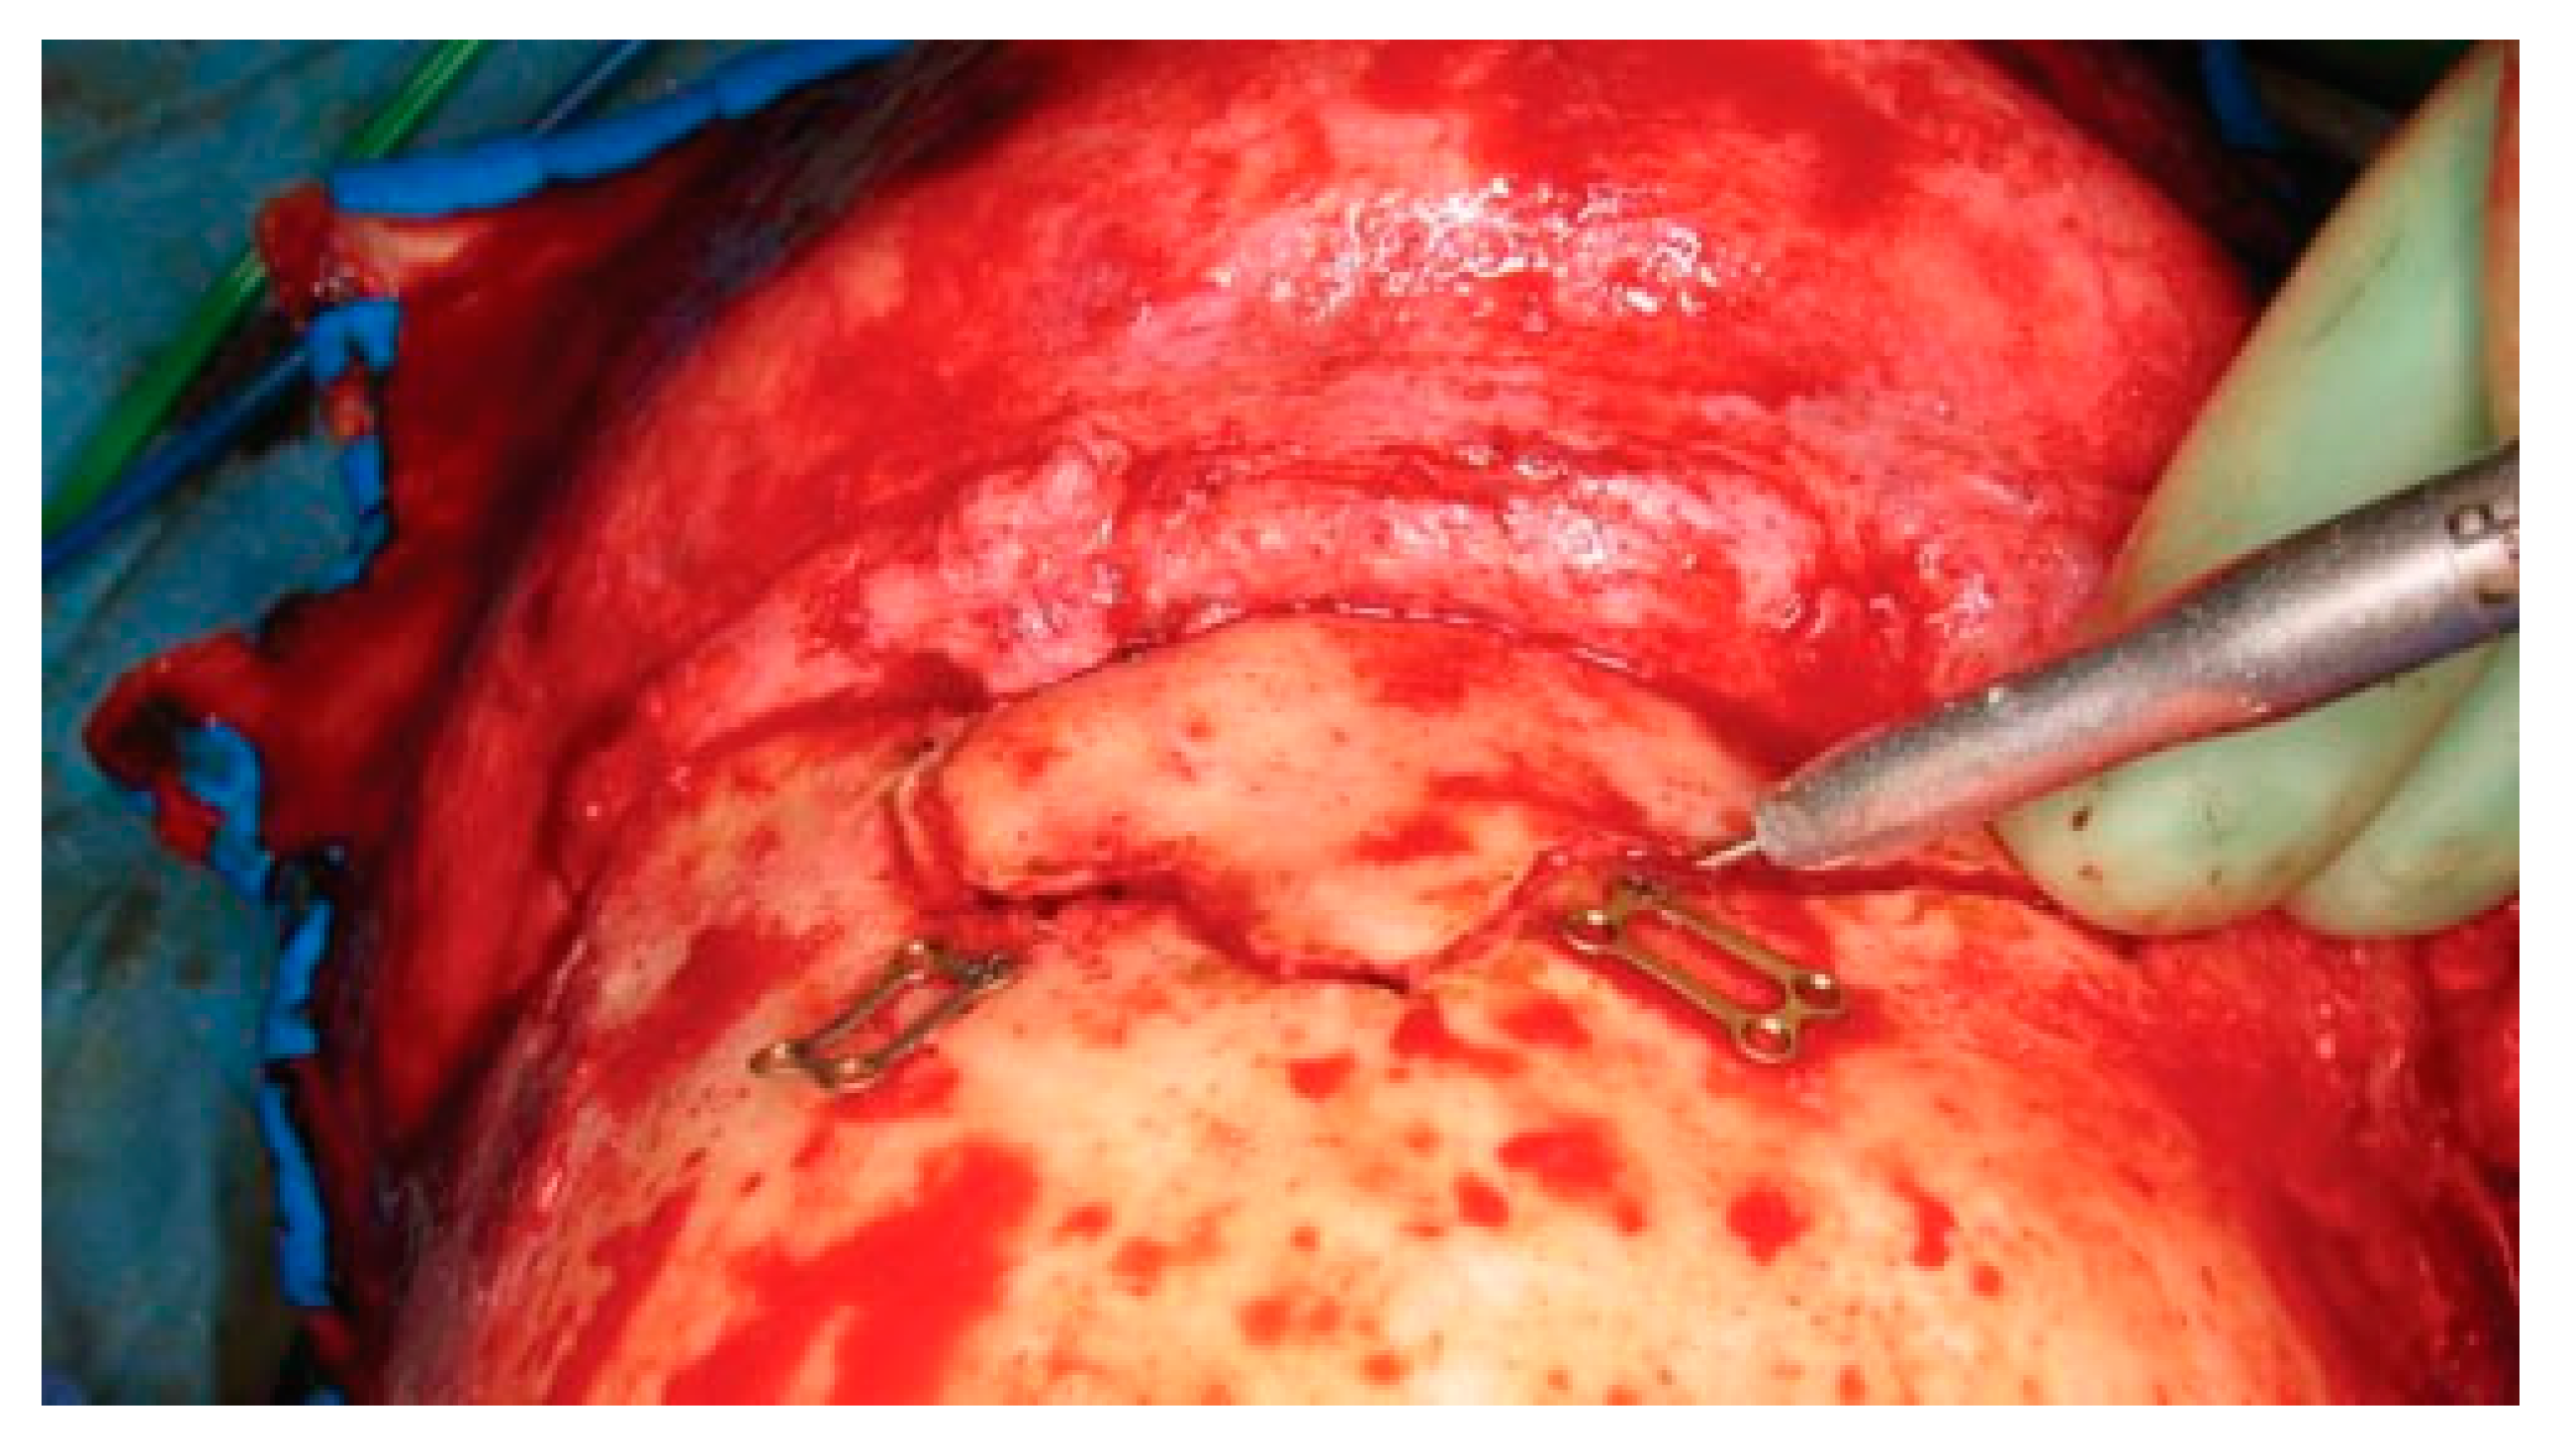

Once the bone fragments are mobilized, the sinus mucosa should be evaluated. A 30-degree endoscope can be helpful to visualize the sinus and the nasofrontal recess through a limited bone defect. Mucosa involved in a fracture line should be removed to avoid entrapment. The fragments are then reduced and plated with 1.0 to 1.3 microplates. Small gaps (4 to 10 mm) can be reconstructed with titanium mesh. Hydroxyapatite bone cement should not be used to fill bone defects. It has an unacceptably high risk of infection and extrusion. However, bone pate, burred from intact calvarium, can be used in combination with a pericranial flap to smooth surface irregularities. During wound closure, it is important to resuspend the temporal soft tissues to avoid long-term ptosis of the forehead and upper midface. Two 2–0 monofilament sutures are passed through the temporoparietal fascia and suspended up to the tempo- ralis muscle fascia (Figure 18).

Figure 18.

Intraoperative photo of a suture used to resuspend the scalp and midface during closure of the coronal incision.